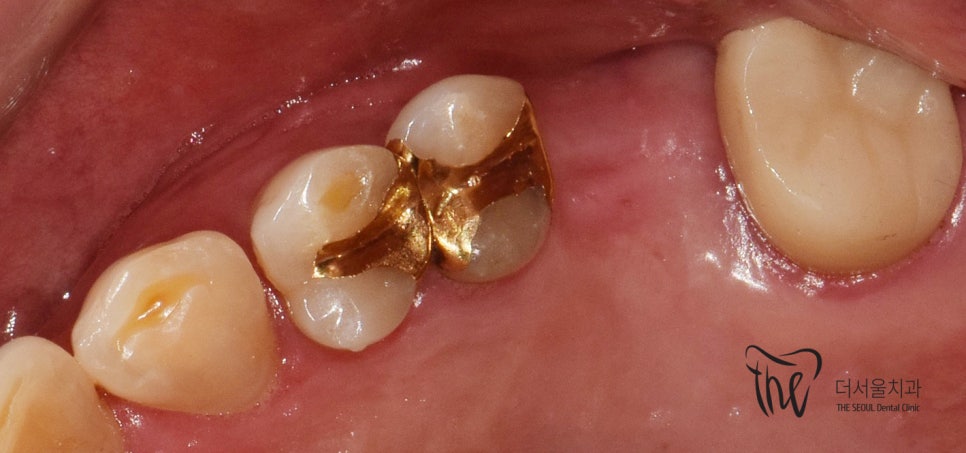

그러면서 제거 수술을 고려하고 있었는데,

뼈와 통째로 쉽게 떨어져 나가버렸습니다.

그리고, 저 자리에 있었던 것들은

사진에서 보실 수 있는 것 처럼 3조각이 나서

구강 밖으로 나와버렸습니다.